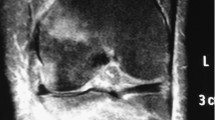

Many individuals with spinal cord injury (SCI) rely on wheelchairs as their primary mode of locomotion leading to reduced weight-bearing on the lower extremities, which contributes to severe bone loss and increased risk of fragility fractures. Engaging in a walking program may reverse this vicious cycle, as this promotes lower extremity weight-bearing and mobility, which may reduce bone loss and fragility fracture risk. However, fragility fracture risk associated with the use of wearable robotic exoskeletons (WREs) in individuals with SCI needs consideration. A 35-year-old man with chronic complete sensorimotor SCI (neurological level = T6) and low initial bone mineral density enrolled in a 6- to 8-week WRE-assisted walking program after successfully completing an initial clinical screening process and two familiarization sessions with the WRE. However, after the first training session with the WRE, he developed bilateral localized ankle edema. Training was suspended, and a CT-scan revealed bilateral calcaneal fractures, which healed with conservative treatment over a 12-week period. Opportunities for improving clinical screening and WRE design are explored. The relevance of developing clinical practice guidelines for safe initiation and progression of intensity during WRE-assisted walking programs is highlighted. This case of bilateral calcaneal fractures illustrates that aiming for “zero risk” during WRE-assisted walking programs may not be realistic. Although WREs are a relatively new technology, current evidence confirms their potential to greatly improve health and quality of life in individuals with chronic SCI. Hence, ensuring their safe use remains a key priority.